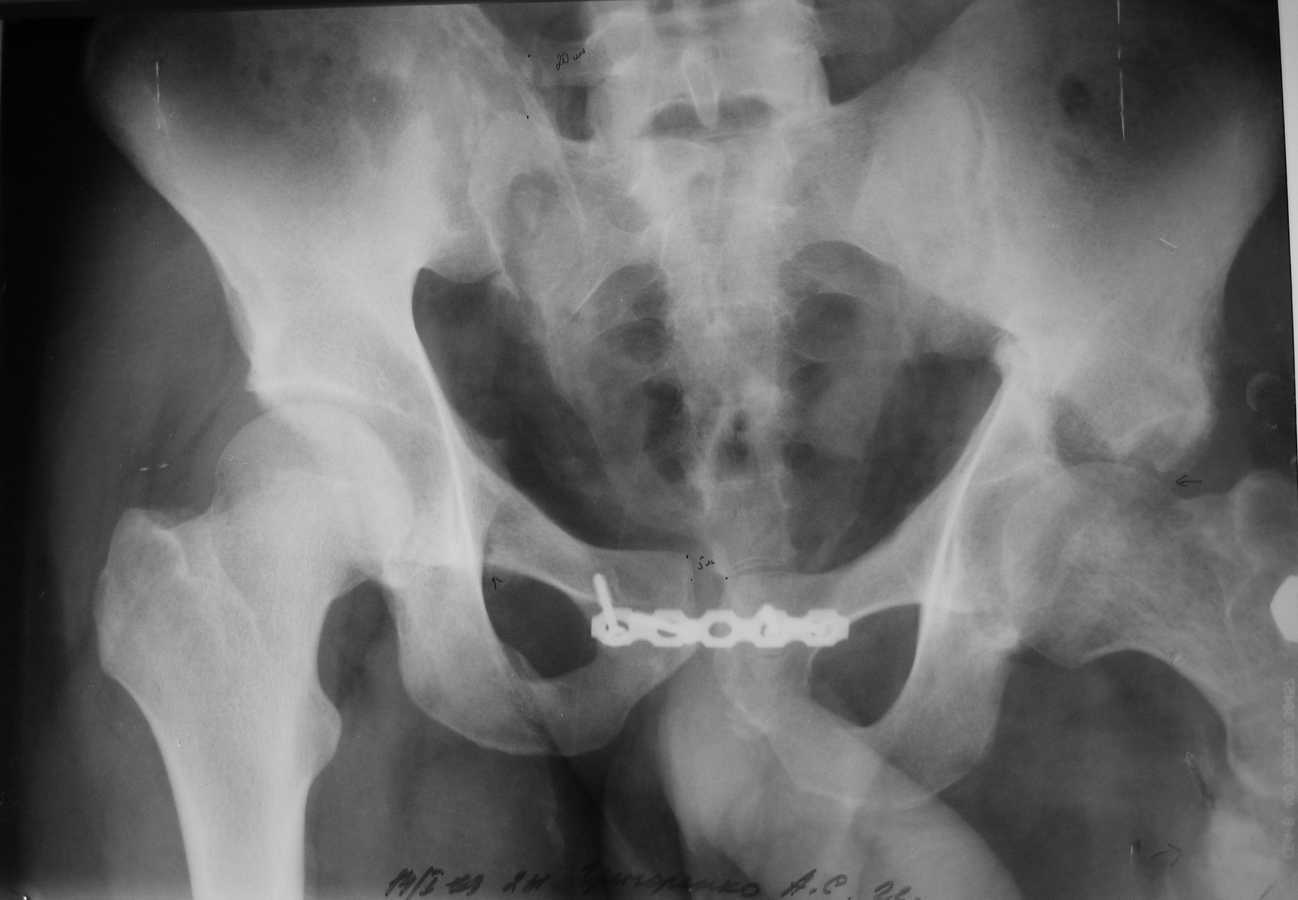

Уважаемые коллеги, у пациента 26 лет имеется дефект в\з бедренной кости образовавшийся в результате СНЭ по поводу травматического остеомиелита

Также имеется травматическая деформация таза с трансвертлужным переломом на стороне дефекта.

Планируется замещение дефекта транспортом кости.

Хотелось бы услышать ваши советы по поводу оптимальной компоновки АВФ (стержневой, спице-стержневой), есть ли необходимость в дополнительной фиксации за кости таза?